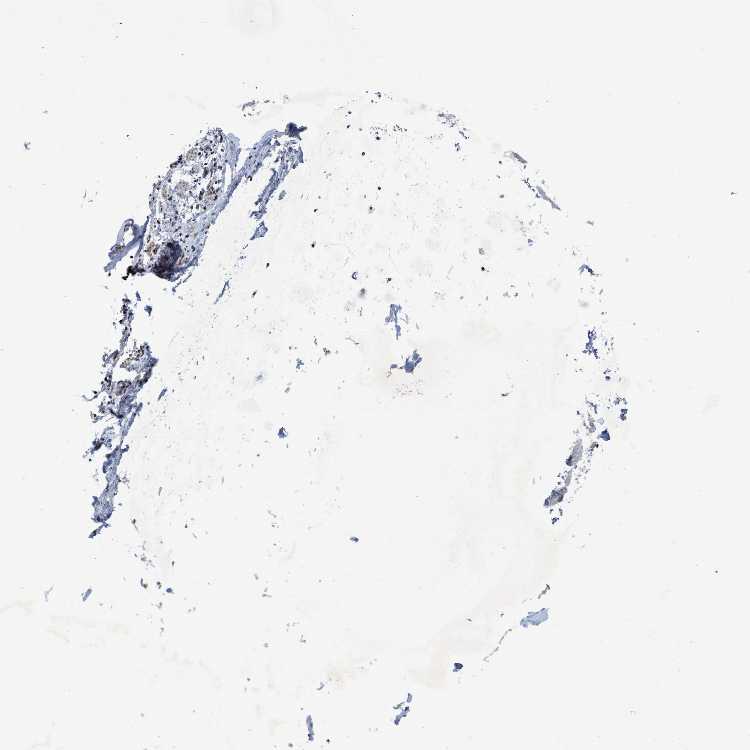

SOFT TISSUE 1 - Antibody stainingi

Antibody staining in the annotated cell types in the current human tissue is reported as not detected, low, medium, or high, based on conventional immunohistochemistry profiling in selected tissues. This score is based on the combination of the staining intensity and fraction of stained cells.

Each image is clickable and will lead to virtual microscopy that enables deeper exploration of all samples and also displays staining intensity scores, fraction scores and subcellular localization as well as patient and tissue information for each sample.

Antibody HPA020344Antibody HPA024149

Chondrocytes -Not detected

Fibroblasts Not detectedNot detected

Peripheral nerve Not detectedLow